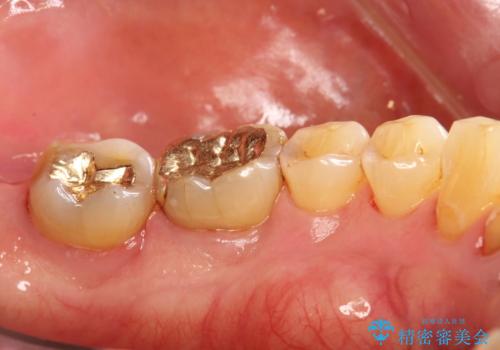

- 定期的にメンテナンスにいらしている方です。日々の歯磨きチェックとクリーニング希望でした。PMTC30分コースと、歯磨き指導を行いました。

歯垢染色液を使うと、一見きれいな歯でも染まっている所が全て歯垢(プラーク)なのがはっきり分かります。歯に付着した歯垢(プラーク)は肉眼では認識しにくいものです。完璧に磨けているつもりでも、磨き残しが残っているかもしれません。

そのため、歯科医院にて定期的に歯磨きのチェックや専門的な機械でのクリーニングをすることが大切です。